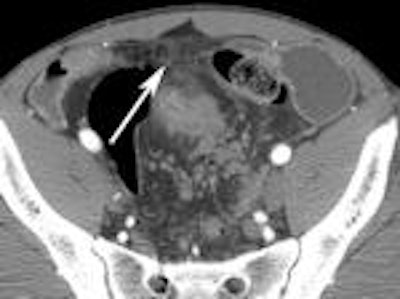

The following images from Higgins' study illustrate some of the clinically relevant findings about Crohn's disease that can be made with CTE.

Left: Mesenteric stranding. Right: Extraluminal gas.